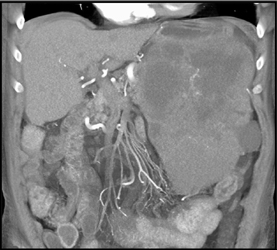

GIST Tumor